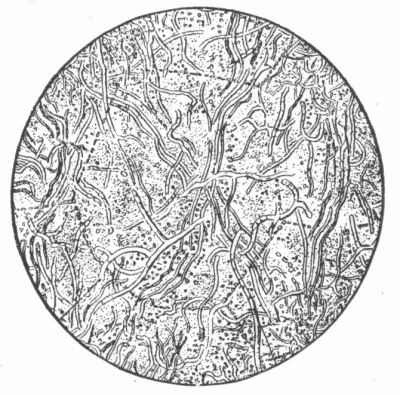

Fig. 6.

A normal sweat-gland, highly magnified. (After Neumann.)

a, Sweat-coil: b, sweat-duct; c, lumen of duct; d, connective-tissue capsule; e and f, arterial trunk and capillaries.